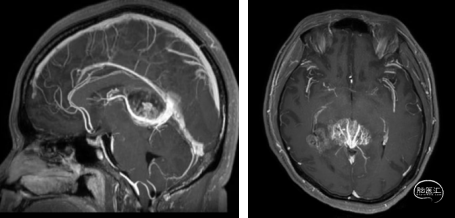

术后

本例患者影像学上表现为累及胼胝体压部的典型的蝴蝶状胶质瘤,病变累及双侧半球,非对称分布。手术均用右侧顶枕叶造瘘+左侧纵裂入路,术中先后探查和分块切除大脑镰后部两侧的病变。大脑镰后部毗邻大脑深部静脉系统,需要尽可能避免损伤Galen静脉或下矢状窦等重要结构,左侧纵裂入路可能有利于实现更好的功能保护。位于胼胝体不同部位的蝴蝶状肿瘤,由于解剖基础和功能保护的需求,采取不同的入路,从而在尽可能保护脑功能的前提下安全切除病变。

术后管理要点:严密监测神经系统症状,密切观察患者头痛缓解情况、发热等。术中血性或者炎性脑脊液容易出现三脑室底、中脑导水管部分黏连或者堵塞形成梗阻性脑积水,需要定期复查,制定后续治疗综合方案,若仍不能缓解者则需要手术治疗。